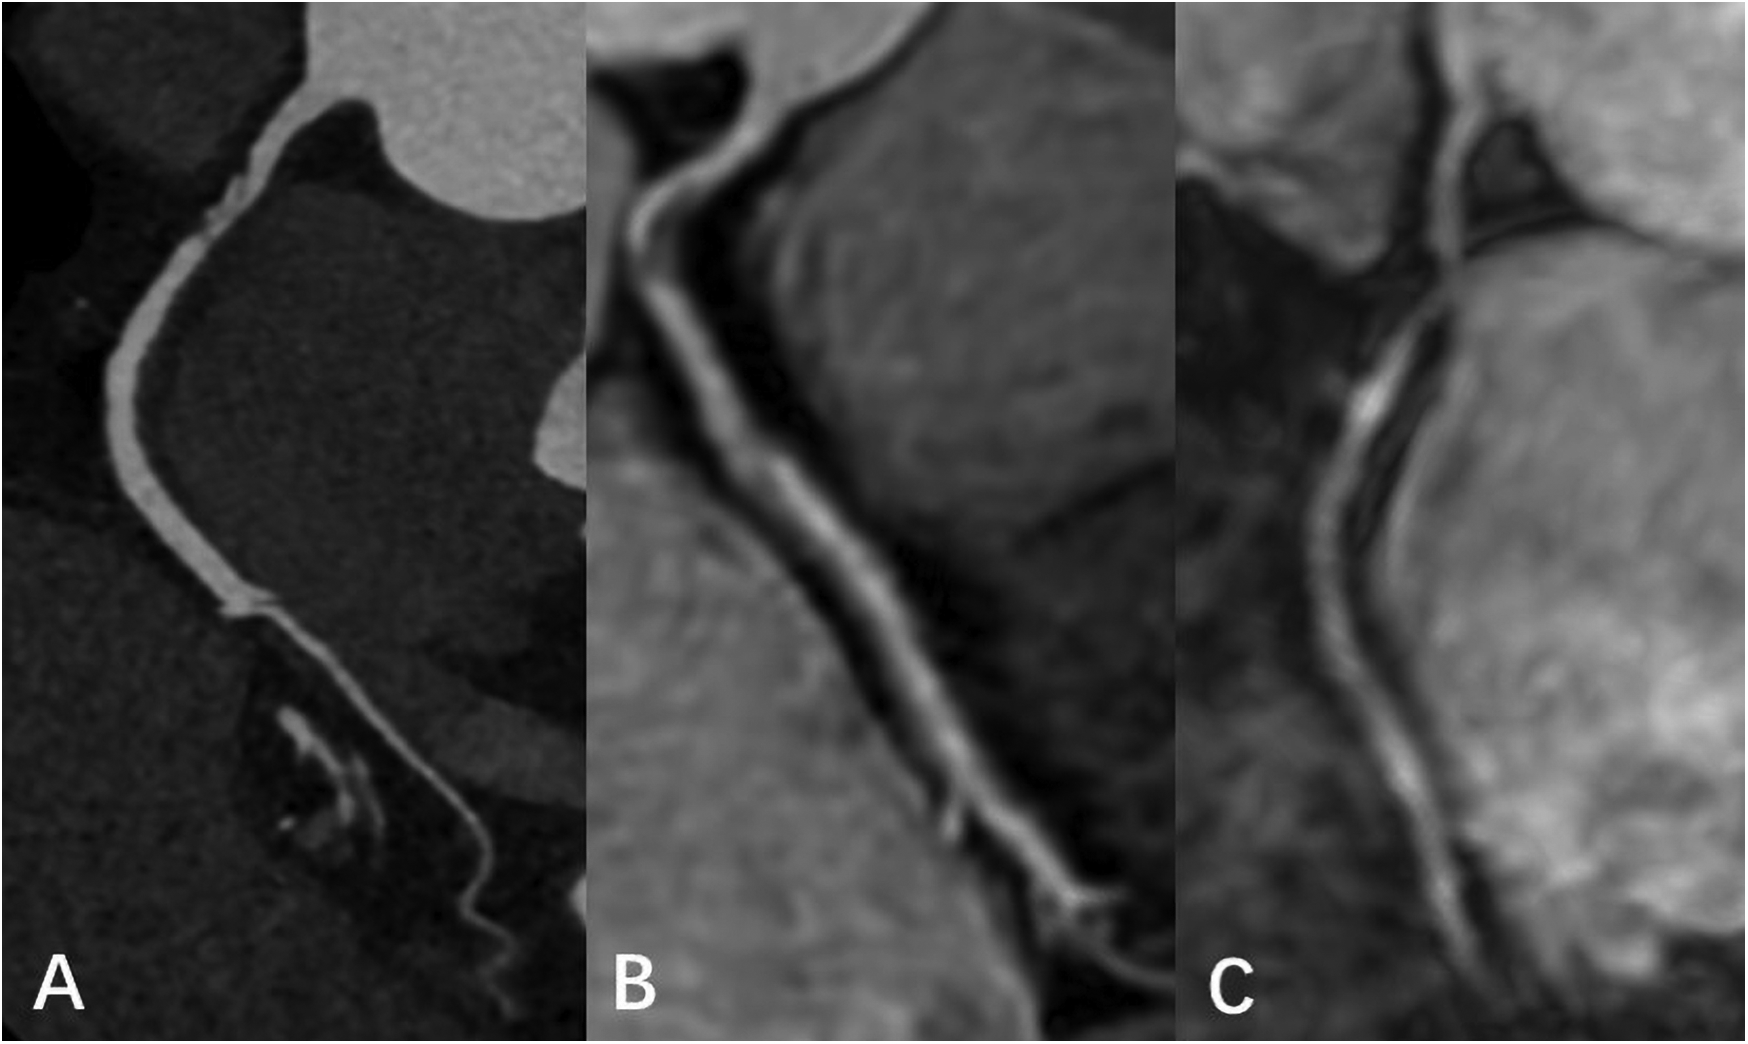

Figure 5

Male, 66 Y, with moderate stenosis of RCA. CTA (A) showed mixed plaque in the proximal segment of RCA with moderate lumen stenosis. 3D BTFE (B) and MSG-EPI (C) also showed local moderate stenosis of the RCA proximal segment.